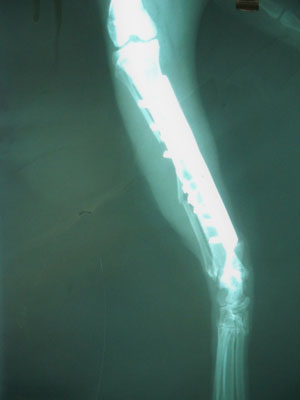

Γάτος 12 μηνών με συντριπτικό κάταγμα μεσότητας κνήμης και κάταγμα περόνης. Παλαιότητα κατάγματος περίπου 2 βδομάδες. Έγινε ανάταξη των 2 μικρών κομματιών με 2 σύρματα. Ακολούθησε ανάταξη των καταγματικών άκρων με πλάκα 2.7mm. Τοποθετήθηκαν 5 κοχλίες στο κεντρικό κομμάτι και 3 στο περιφερικό (2.7mm).

Χειρουργοί : Πούπαλος Γιώργος, Σιδεράς Δημήτρης